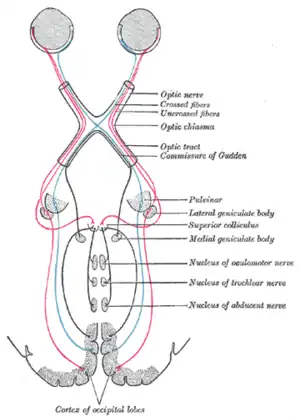

Parinaud's syndrome results from injury, either direct or compressive, to the dorsal midbrain. Specifically, compression or ischemic damage of the mesencephalic tectum, including the superior colliculus adjacent oculomotor (origin of cranial nerve III) and Edinger-Westphal nuclei, causing dysfunction to the motor function of the eye.

a,b)Parinaud's syndrome- sagittal and postcontrast sagittal images pineocytoma compressing the midbrain tectum Cross section of midbrain. The area affected in Parinaud's syndrome is indicated by the striped region.

Cross section of midbrain. The area affected in Parinaud's syndrome is indicated by the striped region.